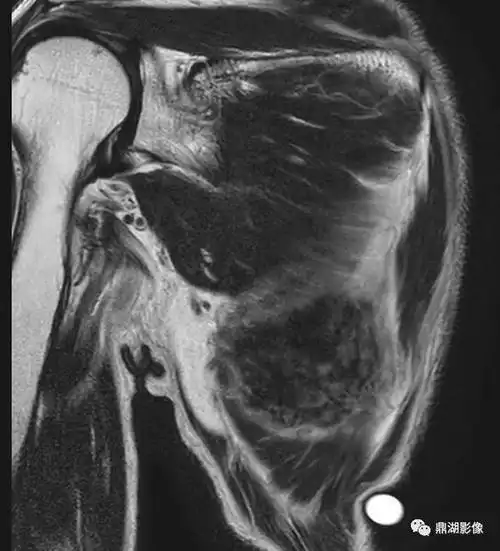

精彩推荐背部弹力纤维瘤超典型影像表现